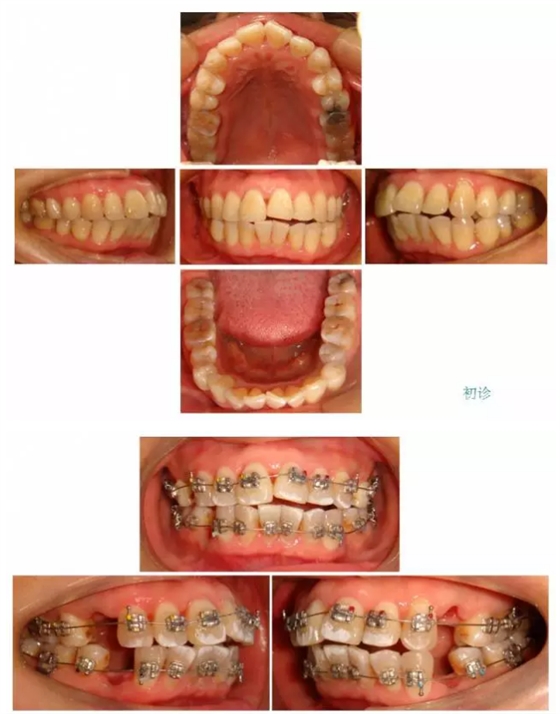

【原創(chuàng)博客】這樣的代償矯治大家滿意嗎?(重度骨性二類)——侯志明